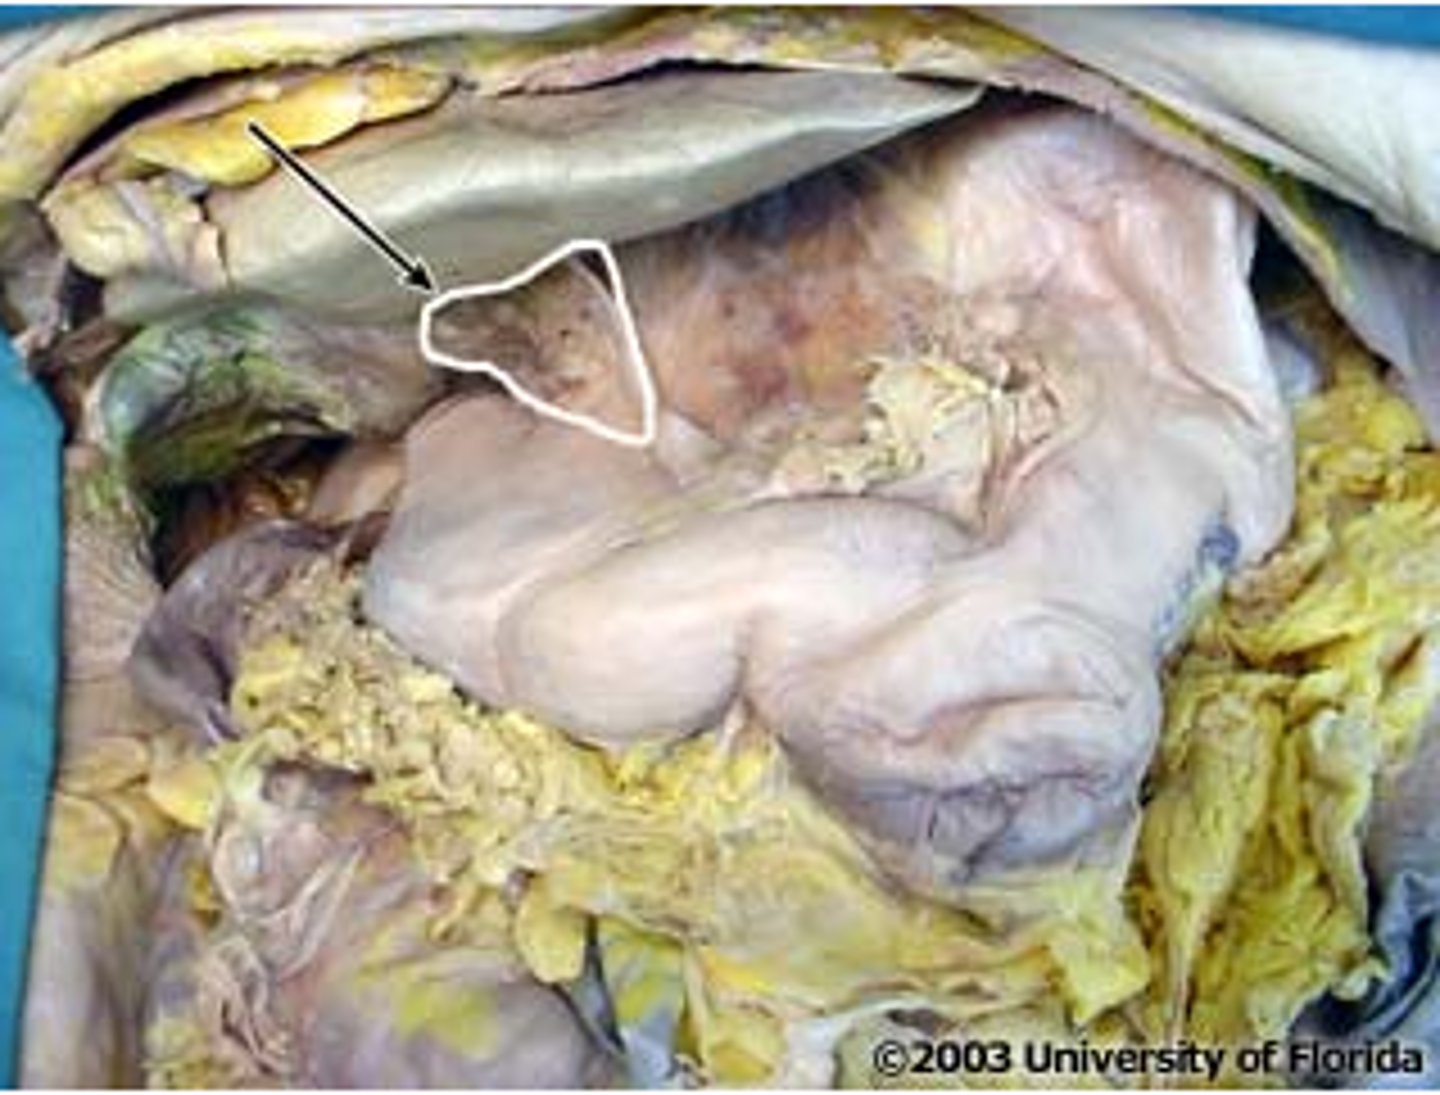

quadrate lobe (of liver)

caudate lobe (of liver)

porta hepatis

where the blood and lymph vessels, bile ducts, and nerves enter and leave the liver